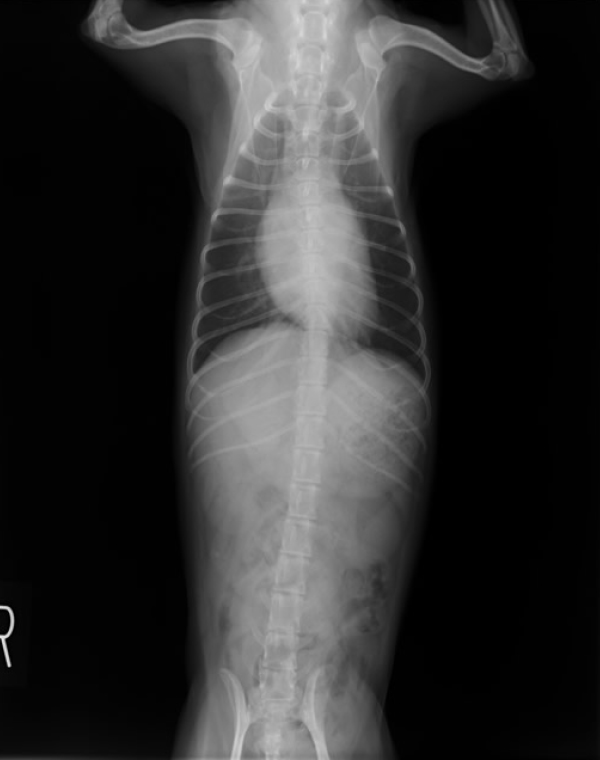

胸部レントゲン検査

X線により心拡大の有無、気管や肺の異常・病変の有無、肝臓うっ血の有無など、内臓の外観の評価を行います。2~3方向から撮影することによって多角的に異常を検出します。

心臓疾患による外観の異常は、たとえば咳の症状が見られた場合には肺や気管にも変化が見られるなど、心臓以外にも現れることがあります。胸部レントゲン検査はスクリーニング検査としても、診断の確度を上げる意味でも重要です。また、犬猫の心臓疾患は肺水腫や胸水を二次的に引き起こすことが多いため、その確認をする上でも有用となります。

正常心陰影(小型犬)

心拡大、肺水腫(小型犬)